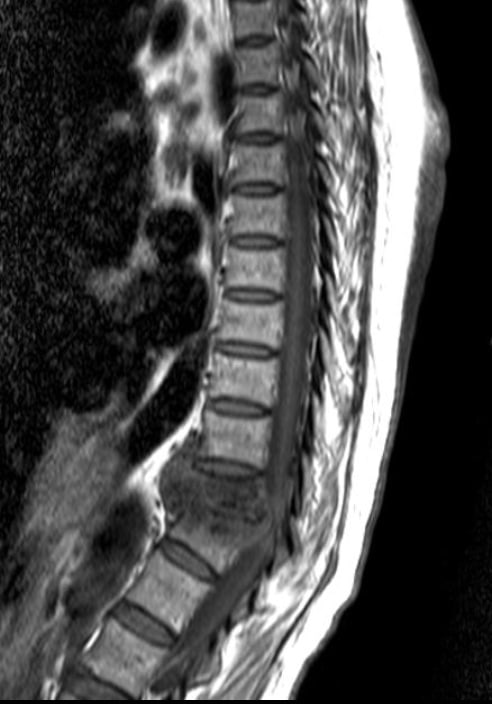

- Các đặc điểm bao gồm sự không đều của bản tận và cả mặt trước của thân đốt sống, với sự phù nề của tủy xương trên MRI.

- T1: giảm tín hiệu tủy xương ở các đốt sống liền kề

- T2: tăng tín hiệu tủy xương, đĩa đệm, mô mềm nhiễm trùng

- T1 C+ (Gd): tăng cường nhìn rõ hơn tuỷ xương, dưới dây chằng, đĩa đệm, màng cứng

Các hình ảnh sau trích từ CT và MRI của một bệnh nhân lao cột sống.